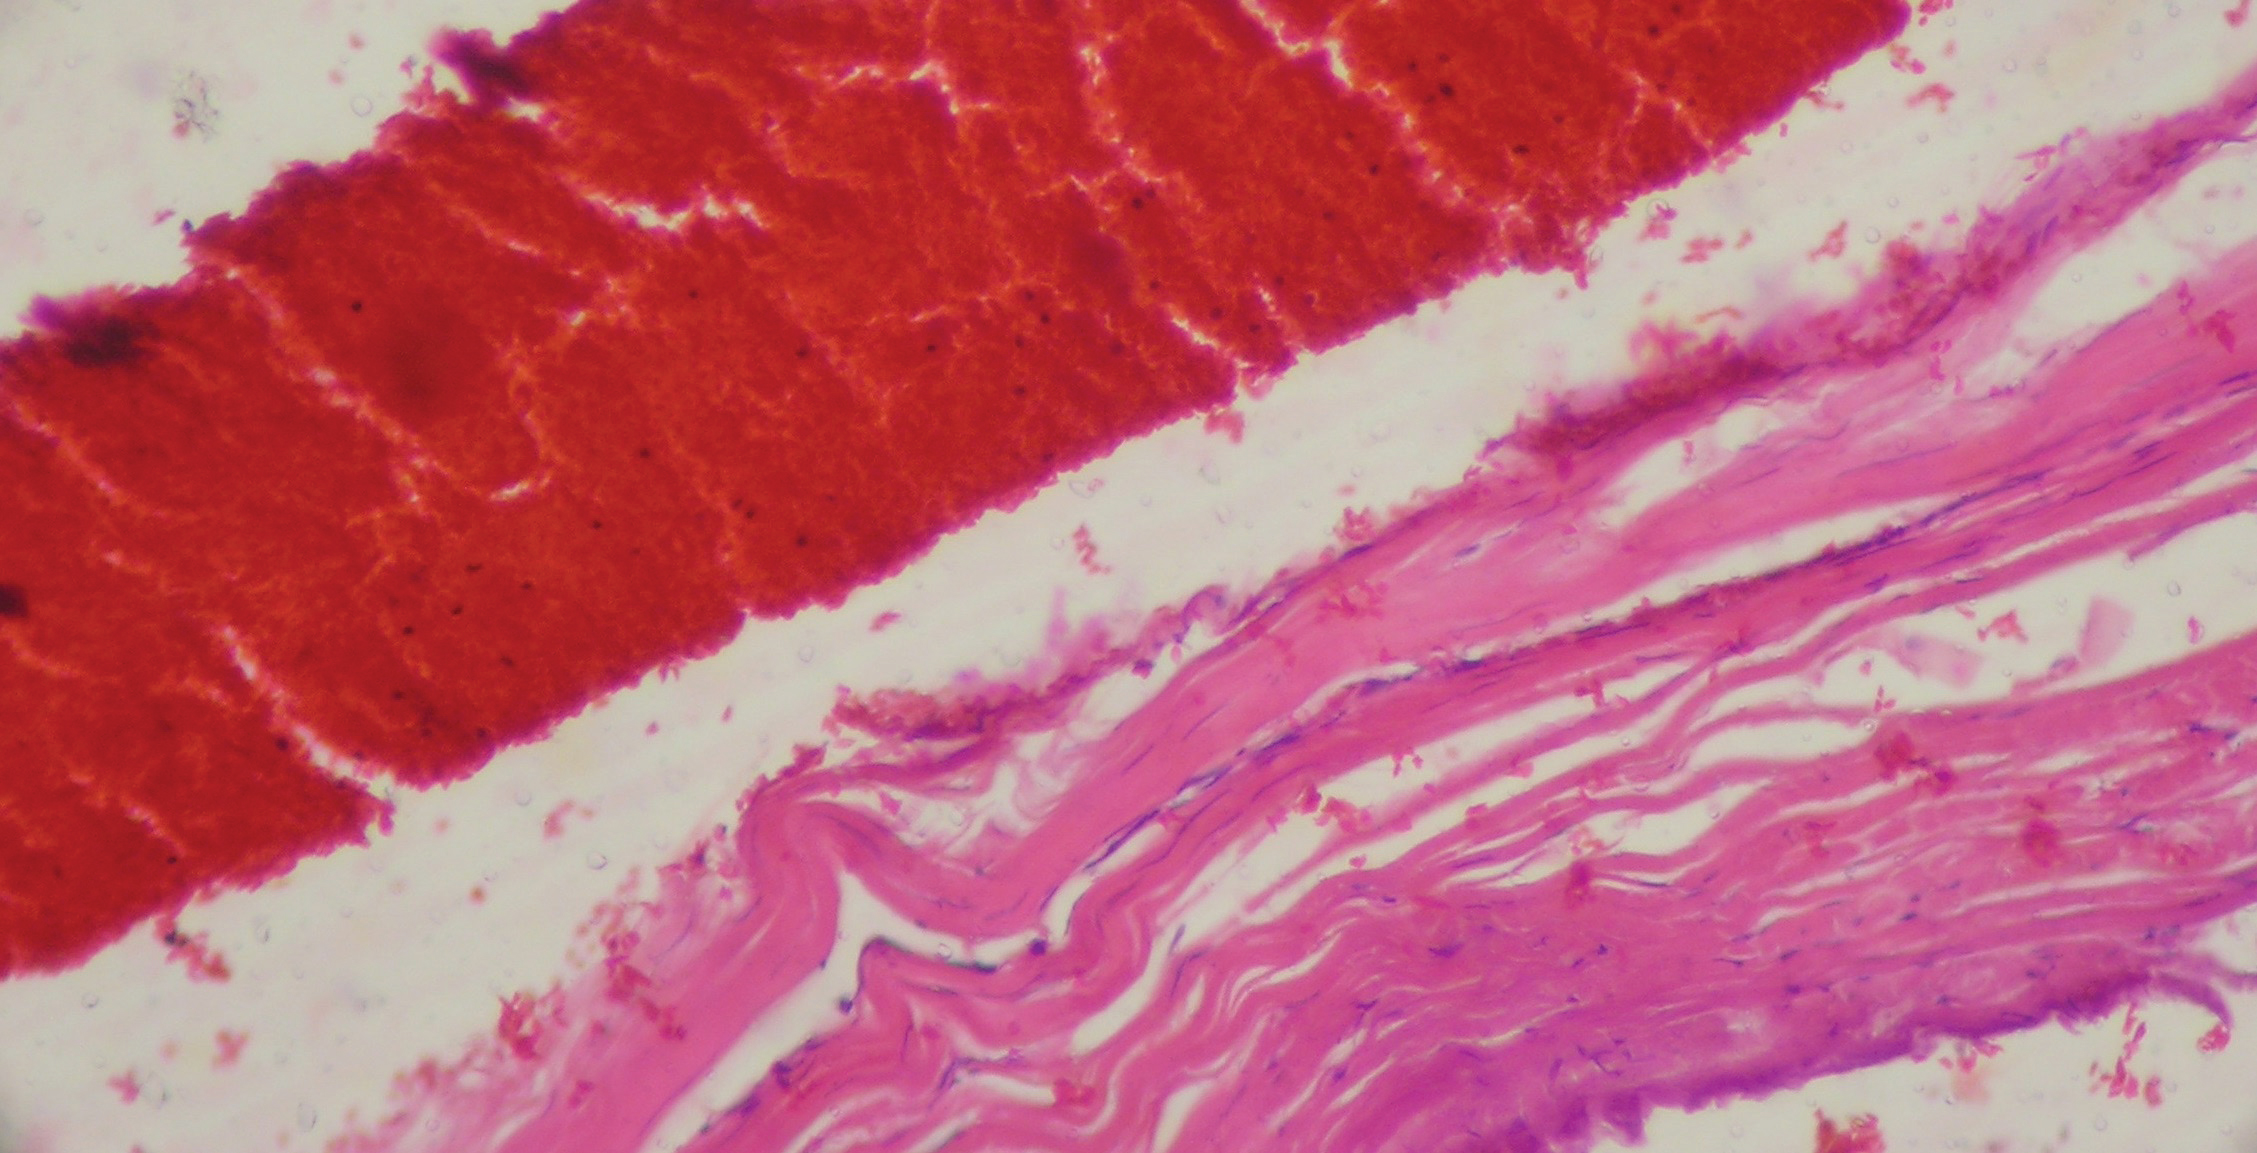

Инкапсулированные СГ отличаются отделением содержимого гематомы от ТМО новообразованной наружной капсулой различной степени зрелости. Образование внутренней (со стороны паутинной оболочки) капсулы с покрытием всей площади СГ необязательно. Так, у всех инкапсулированных СГ внутренняя капсула отсутствовала либо представляла собой не связанный с паутинной оболочкой фрагмент наружной капсулы, отслоившийся от последней за счет вторичных интракапсулярных кровоизлияний (ВИК). В части капсул ВИК принимали характер интенсивной геморрагической имбибиции с распространением вдоль поверхности ТМО и расслоением капсулы СГ с формированием вторичных субдуральных и интракапсулярных гематом (рисунок 2). Не исключено, что подобное расслоение капсулы является основным, а возможно, и единственным механизмом формирования внутреннего и наружного листков хронических СГ, по крайней мере в проекции участков мозга без травматических и воспалительных повреждений.

Рисунок 2. Капсула СГ с наличием множественных ВИК. Отмечается слияние ВИК с отслоением капсулы от ТМО и формированием интракапсулярной полости, заполненной кровью. Окраска гематоксилином и эозином. 129х.